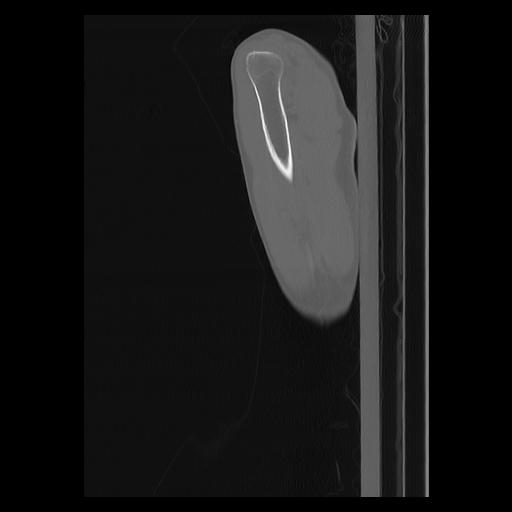

33 PULMON,CE,Sagittal,3.000,PULMON,Sagittal,